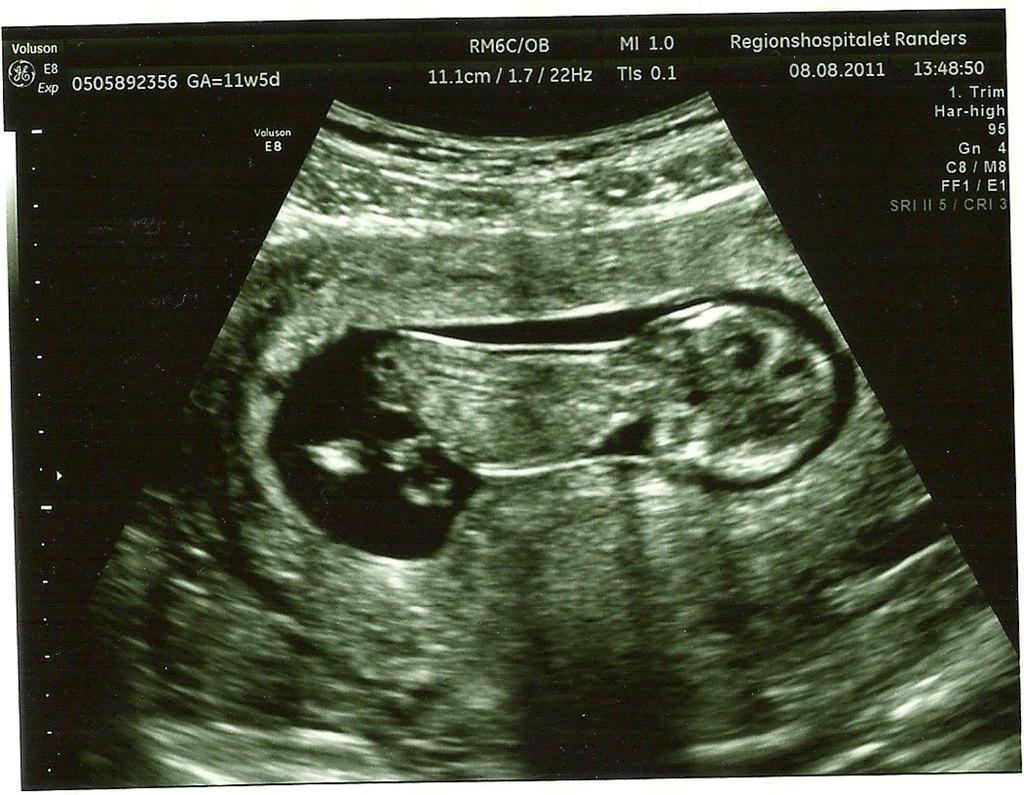

Ja så var det endelig tid til NF - alt så fint ud og det var et MEGET aktivt lille væsen der gemmer sig derinde - mere stolt kan man ikke være og storsøster syntes det er så sejt at vi nu har billeder af babyen!

På billedet med numsen i vejret